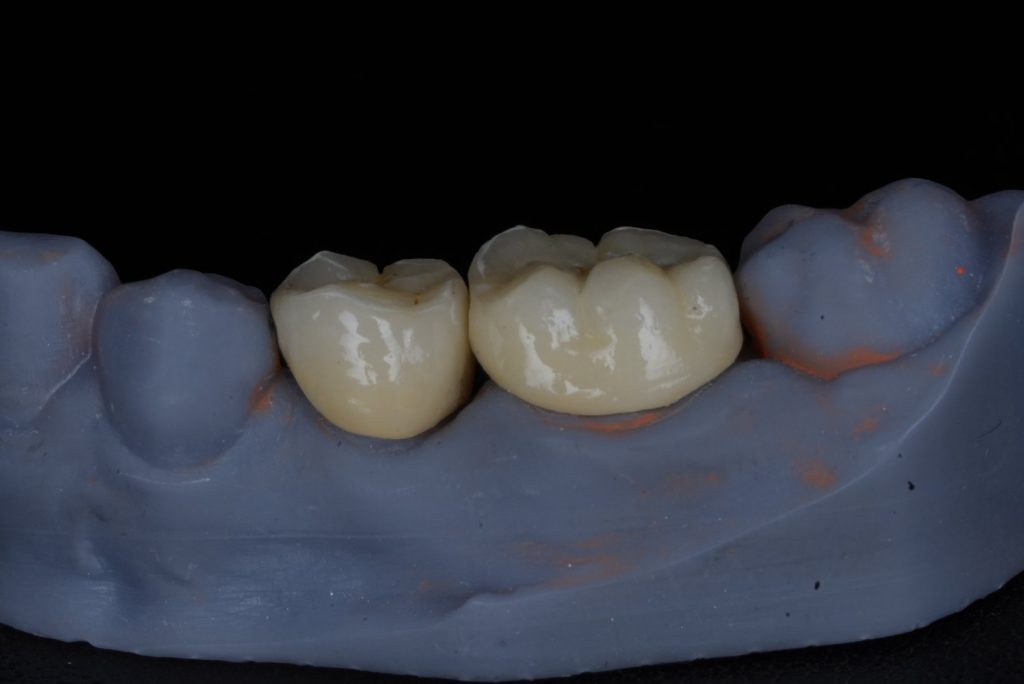

A dual-cure resin core (Clearfil DC Core Plus) was bonded using 4th-generation adhesive (Clearfil SE Bond 2). Tooth preparation followed the principles of adhesive ferrule preservation with rounded internal line angles (Fig 2).

- Fig 2: Post-endodontic core build-up and crown preparation.